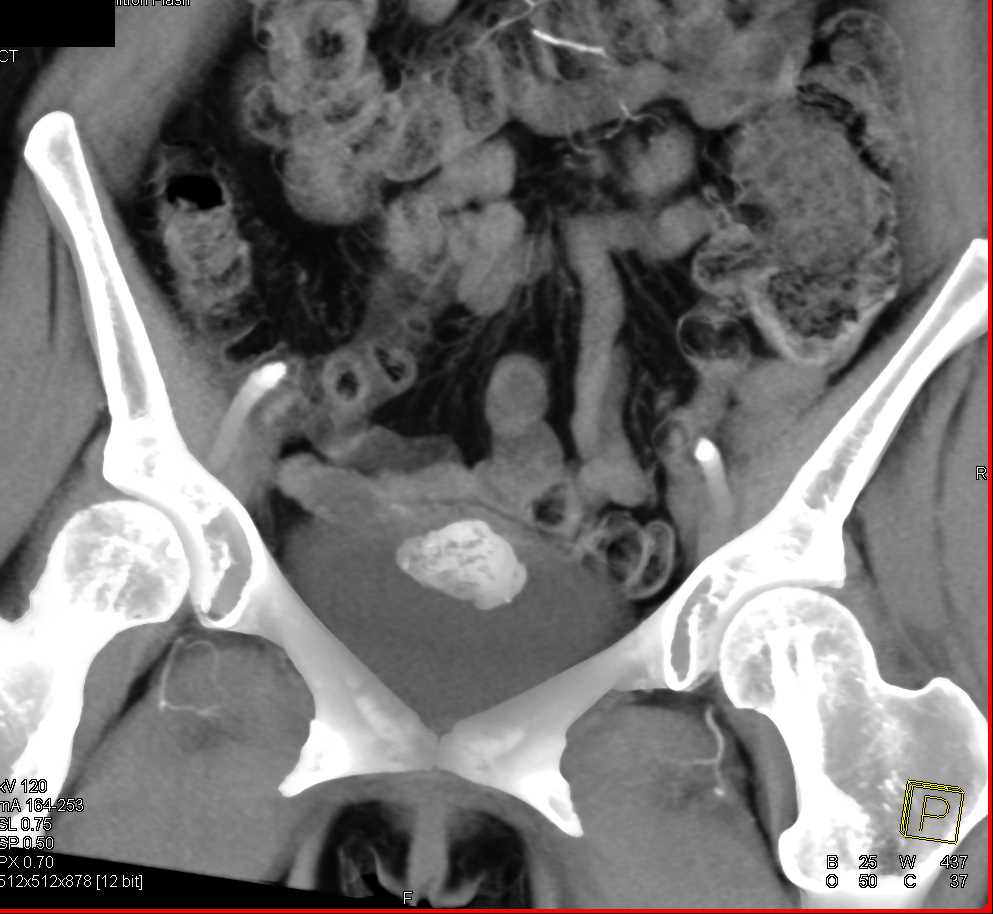

Urachal Carcinoma of the Bladder